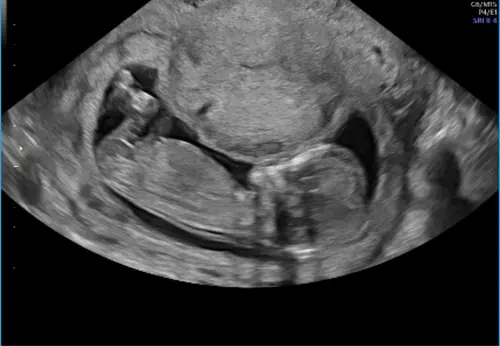

Hallo, op deze echo kan je geen NUB zien helaas.

Zie je het hierop?

Ik zou gokken voor een jongen.

De nub ligt praktisch in lijn met de ruggengraat, dus ik zou mijn gokje wagen op een meisje. Maar kan ook een vertekend beeld zijn van de echo. Spannend!

Ik heb de uitslag, het is een meisje 馃グ馃┓